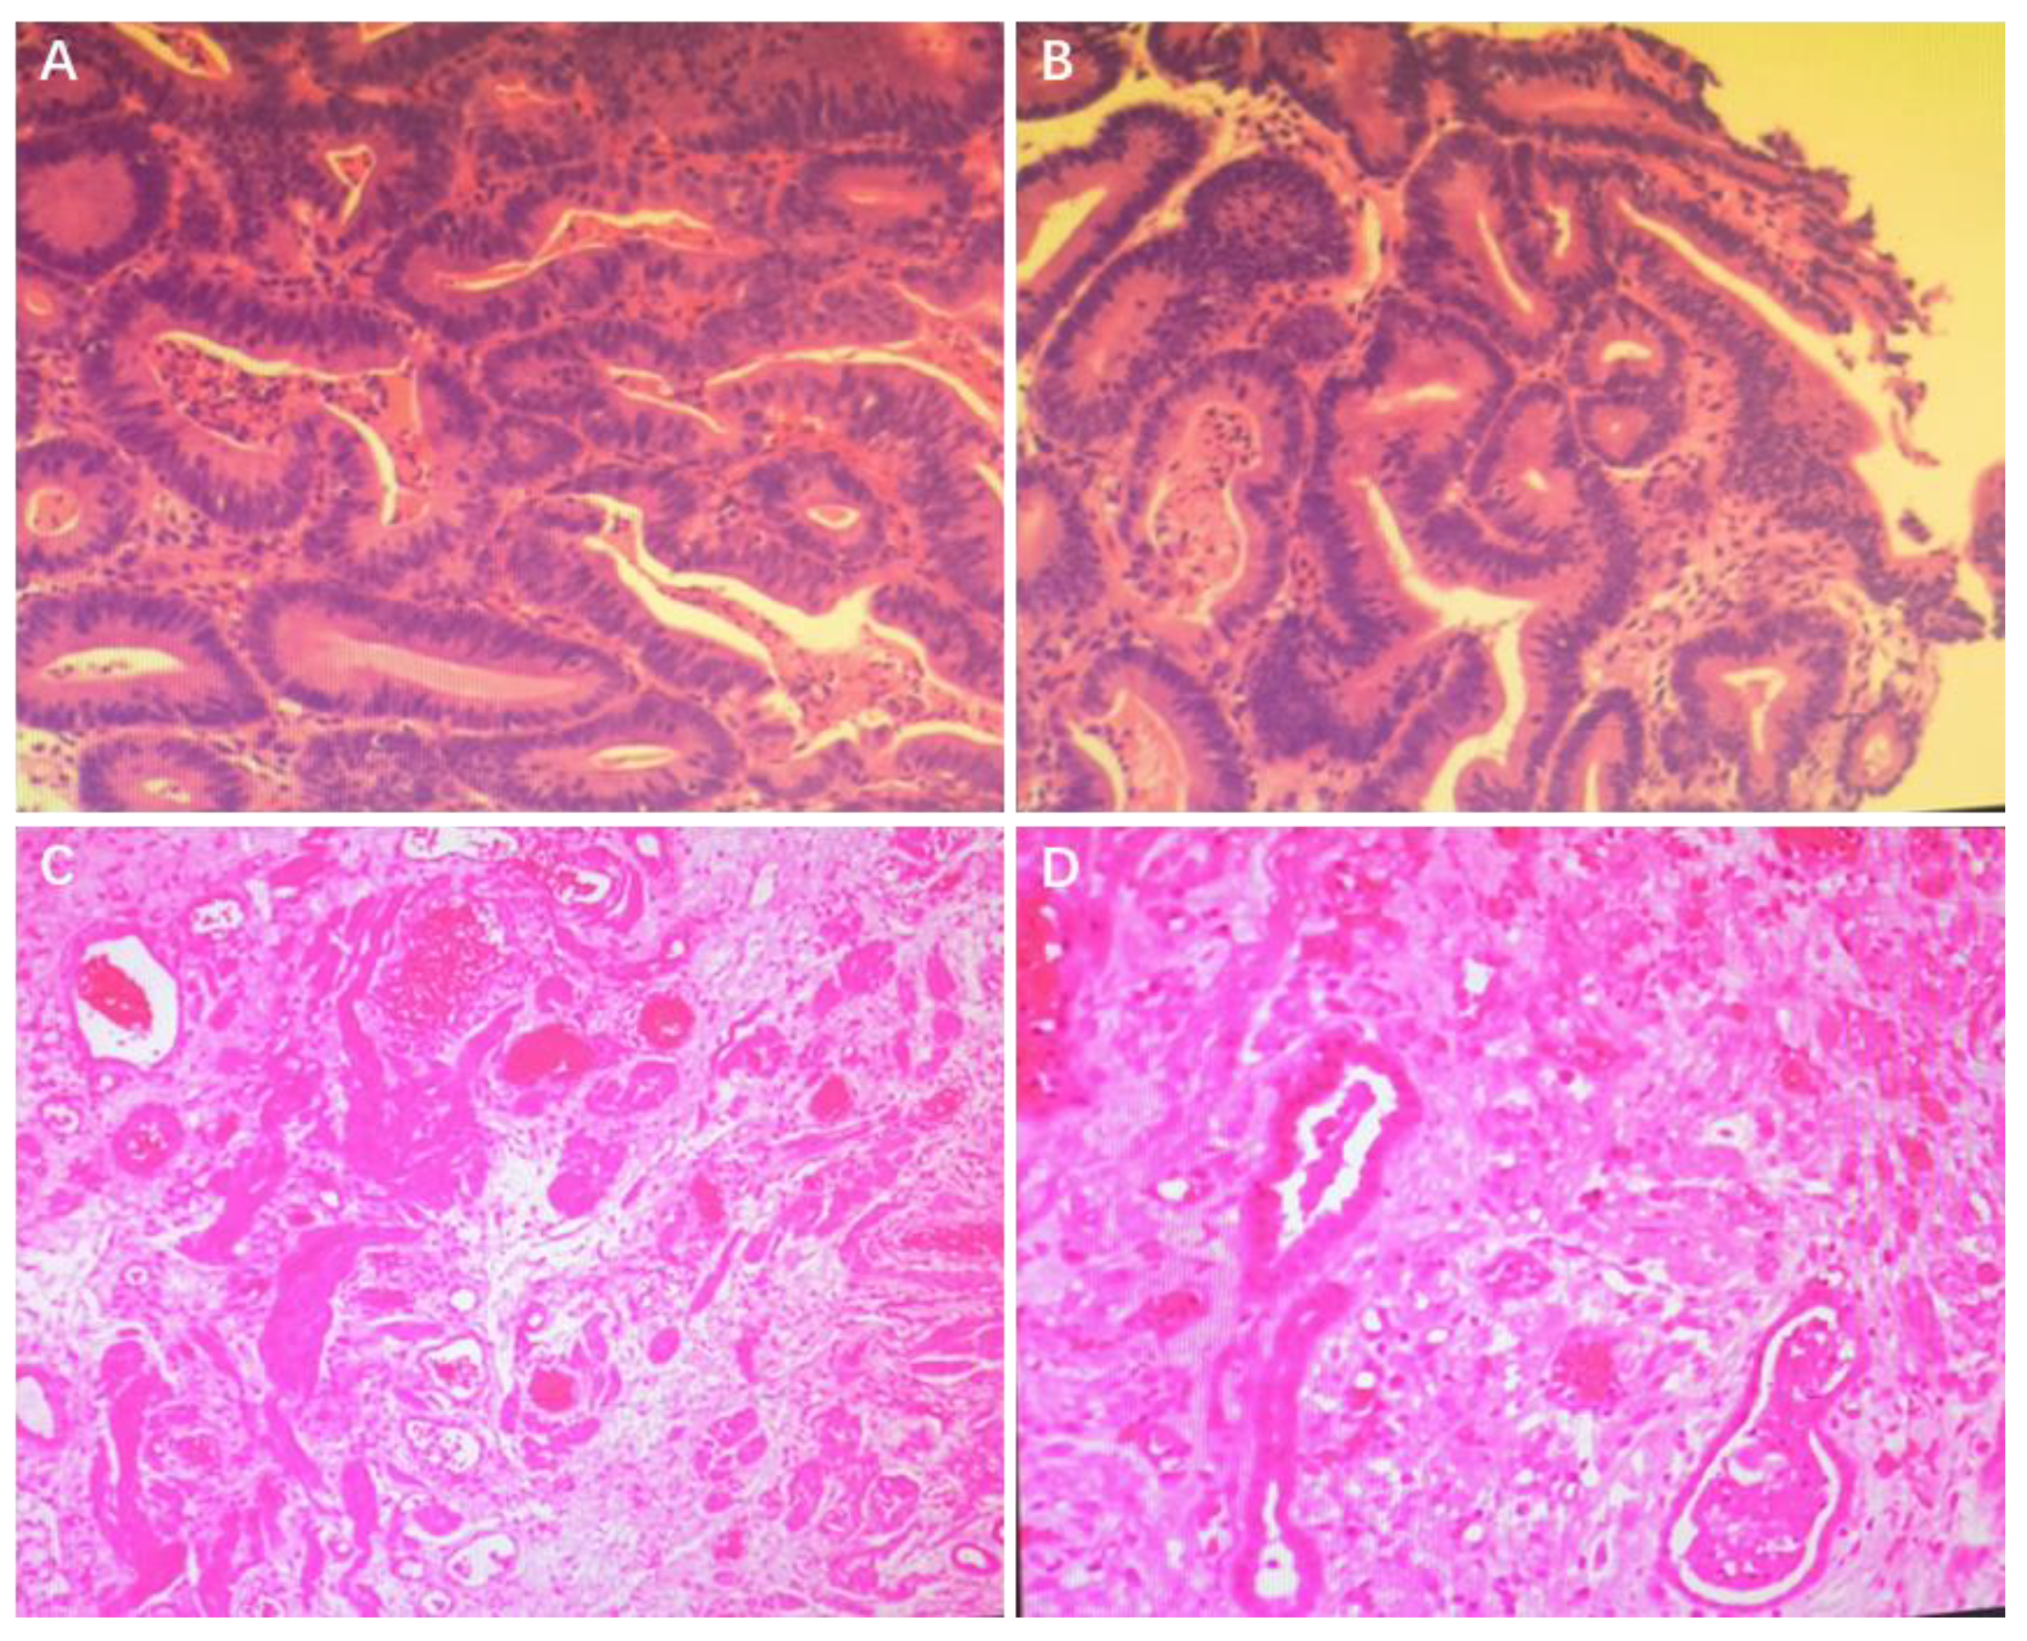

2. Case Presentation